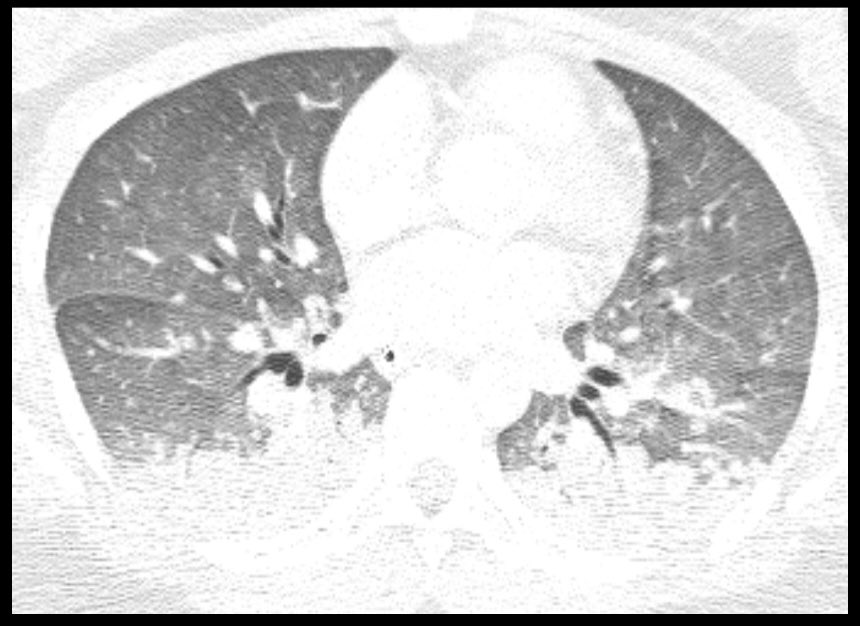

It’s important for us to recognize the various patterns of #COVID19 on CT, but as @thoracicrad and @RadiologyACR have stated, CT should NOT be used as screening. #FOAMrad #FOAMed

@thoracicrad

Society of Thoracic Radiology

6 years

To help familiarize radiologists with the chest CT appearance of #COVID19, RAIOSS & Livon Saúde have begun publicly sharing complete chest CT stacks (scrollable, window/level-able) of confirmed cases for educational and training purposes. https://t.co/5jVbEQQnzE